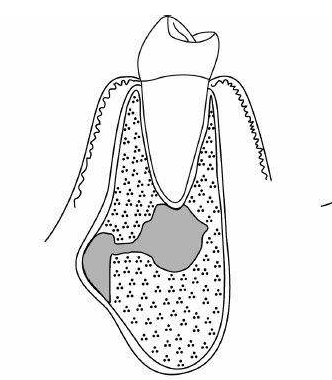

處理根尖周炎的最終方法是進行“牙根端切除手術” 在這一手術無法去除金屬結構的時代裏,採取削去根尖附近骨骼,堵住從根尖方向開始積攢污垢的根管這一辦法。封鎖根尖部位時使用水銀化合物汞合金,但由於會出血,這種方法造成汙物混入的可能性較高,可能導致封閉不徹底及汞合金自身產生異物性,無法達到完美的治療效果。

儘管存在骨折的風險,但如今去除金屬結構已成為可能,治療標準和方法也發生了微妙的變化。X光檢查的結果顯示,根管填充沒有問題的情況下,從根尖方向開始的封閉不易進行。這不光是因為根管內積攢了污垢,還因為手術失敗後病情反復發作造成。從臨床情況來看,牙根端切除手術的治癒率大約為10%。拔牙前人們容易產生“我已經盡力”的想法。

治療的根本目的是去除病因。由於根尖部位完全封鎖,所以應先進行適當的感染根管治療。